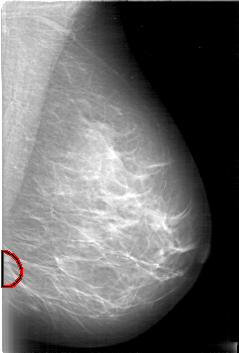

D_4006_1.LEFT_MLO

LEFT_MLO LINES 5281 PIXELS_PER_LINE 3571 BITS_PER_PIXEL 12 RESOLUTION 43.5 OVERLAY

FILE: D_4006_1.LEFT_MLO.OVERLAY

TOTAL_ABNORMALITIES 1

ABNORMALITY 1

LESION_TYPE MASS SHAPE OVAL MARGINS OBSCURED

ASSESSMENT 0

SUBTLETY 5

PATHOLOGY BENIGN

TOTAL_OUTLINES 1

BOUNDARY